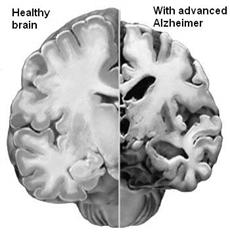

Il cervello di un individuo affetto da Alzheimer appare come un pallone sgonfio a causa della continua eliminazione di neuroni. A sinistra c'è un cervello sano, a destra uno malato.

È assolutamente evidente dalle foto precedenti quanto sia dannoso ed ingente il danno che l'Alzheimer reca al tessuto nervoso: il cervello si sgretola, perde di consistenza accartocciandosi su se stesso. Fu proprio questa la visione che portò il dottor Alzheimer a descrivere il cervello malato dicendo che «presentava una scarsità di cellule nella corteccia cerebrale». Inoltre, le cellule rimaste vengono saturate di placche senili di β-amiloide, rendendo complicati i trasferimenti degli impulsi da una parte all'altra del sistema nervoso. Queste placche sono quelle che Alzheimer definì nell'autopsia di Auguste come «gruppi di filamenti localizzati fra le cellule nervose».